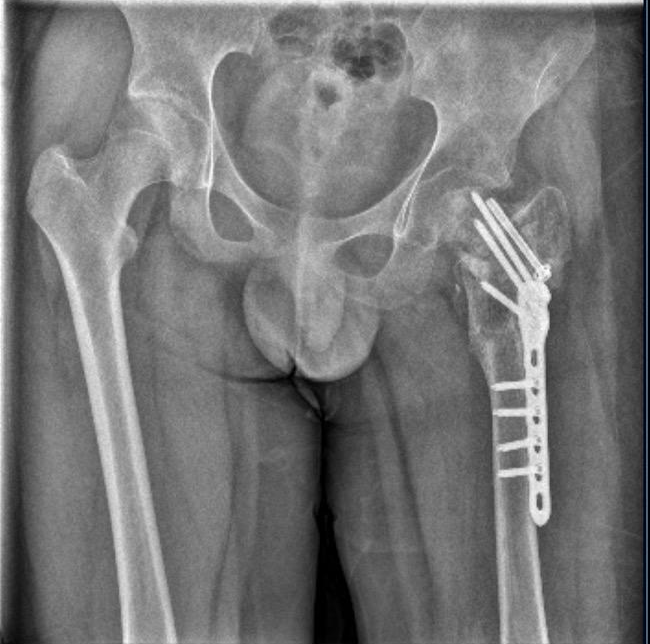

▲小武接受治疗

耽误10天,小武错过了最佳治疗时机。9月9日被妈妈送到泉州市正骨医院,他已是陈旧性骨折。医生说,“刚摔时只是骨裂,如果立刻来医院处理,休息一两个月就好了。”

2023年11月13日出院,小武的诊断结论列出左股骨颈陈旧性骨折、左髋部感染、肺部感染等十余种症状。

▲小武左腿骨折

武女士说,事发两年来,小武共做了六次手术,仅左髋部感染就做了四次手术,但损坏部分依然长不出来。如今,小武骨骼萎缩,拄双拐走路时一瘸一拐,成了“长短腿、粗细腿”。

医生说,小武股骨头坏死已到晚期,只能做康复治疗。他的学业也已荒废两年多。医生还说,后期可能要把胯骨和髋骨置换成人工骨骼。但昂贵的医疗费谁来出,至今没有答案。